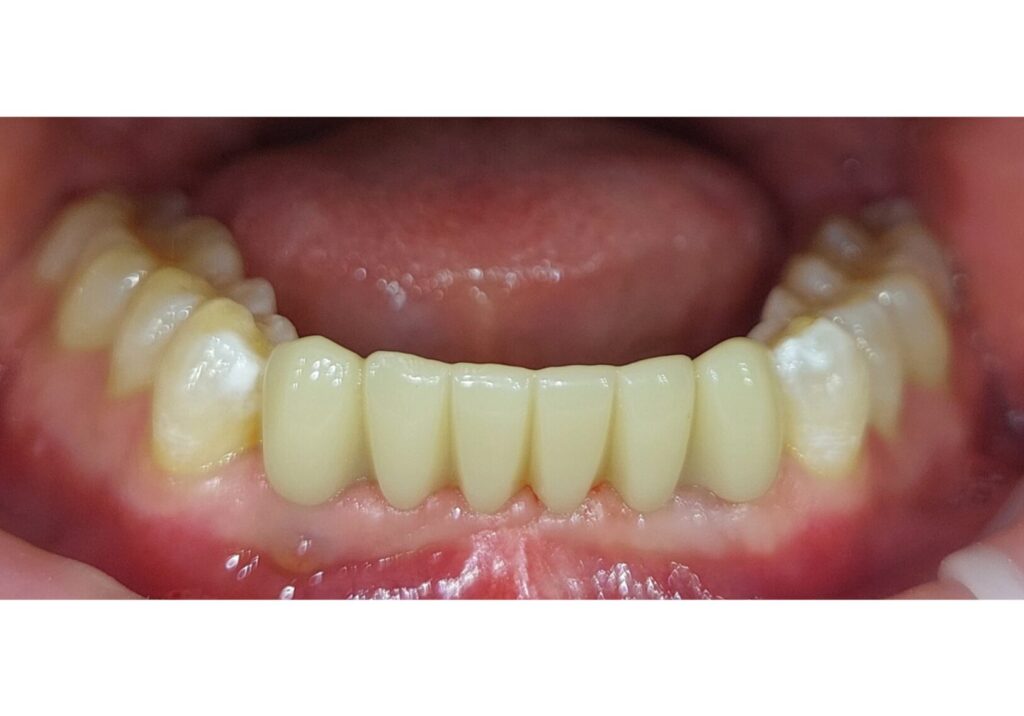

Prieš

Po

Gyd. Aušra Bieliauskienė

Apatinio žandikaulio dalinė išimama plokštelė ir viršutinio žandikaulio 6 priekinių dantų ZrO tiltas. Pacientė kreipėsi dėl sužemėjusio sąkandžio a/ž ir išretėjusių v/ž priekinių dantų. Protezuoti apatinio žandikaulio krūminiai dantys išimama plokštele. Viršutinio žandikaulio dantys atstatyti ZrO tiltu. Nudilę apatinio žandikaulio dantys atstatyti estetiniu plombavimu.

Laisvės pr. 10A, Vilnius

~ 2950 eur

Prisidėję gydytojai: Greta Ardaravičienė